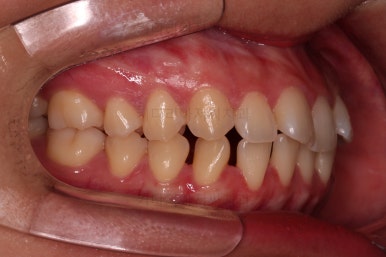

윗니의 배열과 위치는 거의 완성이 되었고요.

아래는 아직 틈이 많이 보이죠.

어금니를 부산치아교정 통해 계속 앞으로 당겨줍니다.

아랫니 틈은 거의 없어졌네요.

대신 여러 교합적인 이유로 아랫니를 좀 더 앞으로 당겨주긴 해야 합니다.